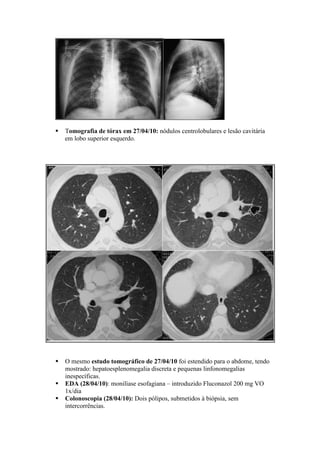

Tomografia de tórax em 27/04/10: nódulos centrolobulares e lesão cavitária

em lobo superior esquerdo.

O mesmo estudo tomográfico de 27/04/10 foi estendido para o abdome, tendo

mostrado: hepatoesplenomegalia discreta e pequenas linfonomegalias

inespecíficas.